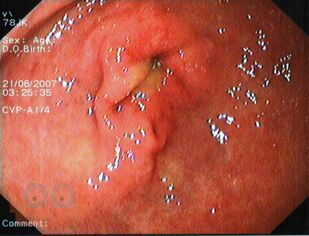

Учебное пособие подготовлено в соответствии с ООП и учебным планом по дисциплине «Пропедевтика внутренних болезней» для обучающихся по специальности 31.05.01 «Лечебное дело». В учебном пособии изложены современные представления о болевом абдоминальном синдроме при заболеваниях органов пищеварительной системы, необходимого для обучающихся при изучении дисциплины «Пропедевтика внутренних болезней». Учебное пособие оснащено тестовыми заданиями и ситуационными задачами различной степени сложности для самоконтроля знаний с эталонами ответов. Учебное пособие предназначено для самостоятельной внеаудиторной работы обучающихся по специальности «Лечебное дело».